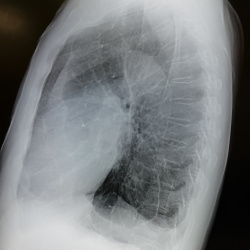

Молодая женщина, жалоб нет. Проходит профосмотр. На ФГ смутило некоторое расширение корней. При контрольном исследовании -на боковой лимфоузлы? или мерещится?